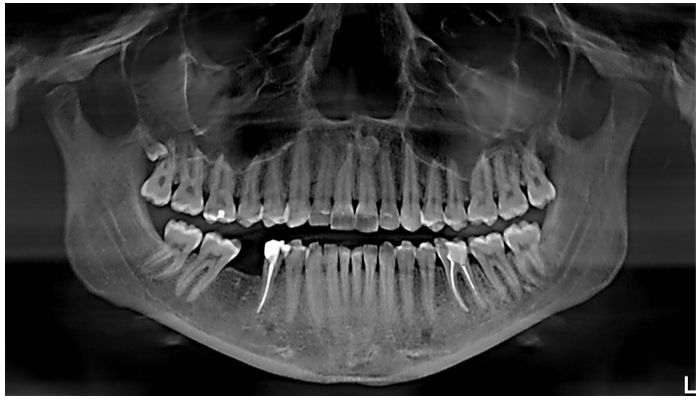

Ортодонтическая коррекция всегда начинается с осмотра и проведения рентгена. Ключевым звеном является ортопантомограмма – объемный панорамный снимок, на котором видны анатомические особенности обеих челюстей: состояние твердых и мягких тканей, корней зубов, гайморовых пазух и височно-нижнечелюстных суставов.

После изучения и оценки рентгенологических данных врач делает слепки, которые отправляет в зуботехническую мастерскую. Специалист воссоздает цифровую 3D-модель зубных рядов и посылает ее производителю элайнеров.